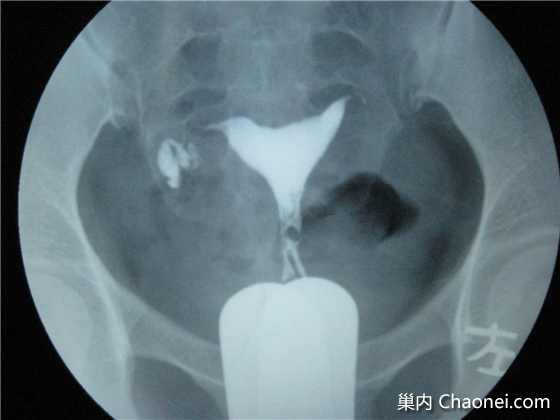

我身边有朋友在备孕过程中遇到输卵管不通的问题,感到无比焦虑,我提议她们尝试通草疗法,开始时,她们半信半疑,但经过几个周期的坚持,她们真的感受到了身体上的改变,医生的检查结果显示,输卵管的通畅性有了明显改善,看到朋友的转变,我也深感欣慰。